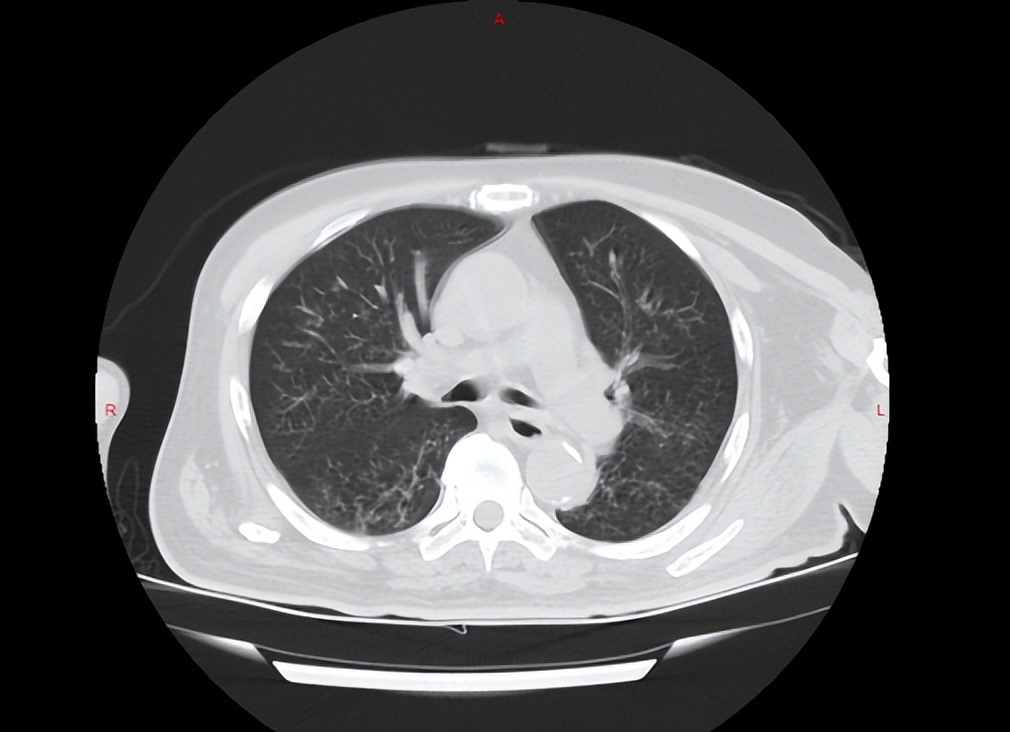

病人为老年男性,近1个月频繁便血,曾多次尝试肠镜检查,但都因肠道准备不佳未能成功,最终病人家属只好求助于鞍钢总医院胃肠外科。病人既往脑血栓病史3年,遗留右侧肢体无法活动,语言不清。因长期卧床、吞咽功能及咳痰能力减弱,病人已出现较为严重的肺炎,吸氧状态下血氧饱和度尚不能完全达标并且病人还患有糖尿病、前列腺增生等多种疾病。

入院后当务之急就是要积极治疗肺炎,解除病人感染、消耗及缺氧的状态;另外通过较为温和长效的缓泻方式清理病人的肠道以完成肠镜的检查;还要给予病人充足的营养来弥补病人长期以来的消耗。最终病人肺炎明显好转,缺氧及营养不良状态得到改善,并完成了肠镜及病理检查,结果回报为结肠肝曲腺癌。